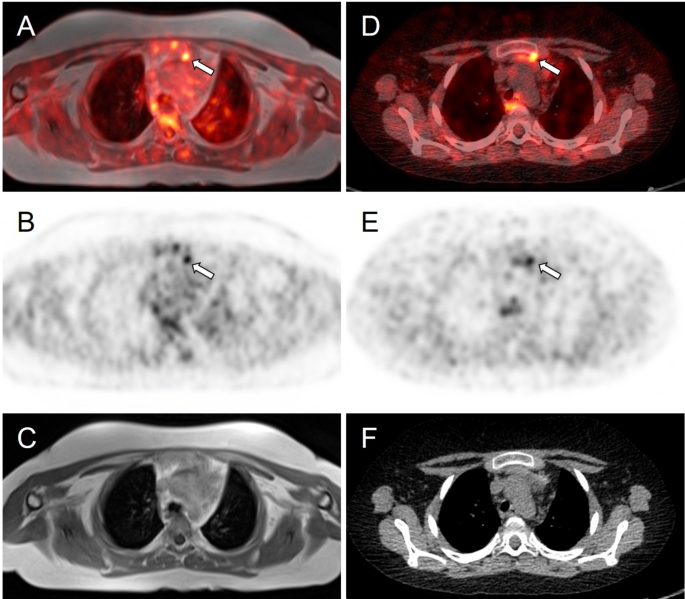

A clinical team of obstetricians, urologists, and endocrinologists discussed the treatment plans for CS and perinatal management. Pharmacological treatment had two problems: radicality and risk of fetal adrenal insufficiency due to placental passage of medication; therefore, we decided to perform adrenalectomy during pregnancy. At 28+3 weeks of gestation, a retroperitoneoscopic adrenalectomy was performed by urologists. After the induction of general anesthesia, the patient lay on the bed in a complete left lateral position (Figures 5A, 5B). Consequently, the endoscope and instrument ports were placed in the same configuration as those used in the conventional retroperitoneal approach for nonpregnant patients. Port placements were planned guided by abdominal ultrasonography to identify the uterine position, and the assistant port was positioned at a location that minimized potential interference with the uterus. The surgery was completed without complications. The operative time was 83 minutes, and bleeding was minimal. Histopathological examination indicated that the tumor was an adrenocortical adenoma (Figures 6A–6C).

Figure 5: Photograph showing the patient in the left lateral decubitus position after general anethesia

(A) Abdominal area and (B) dorsal area.